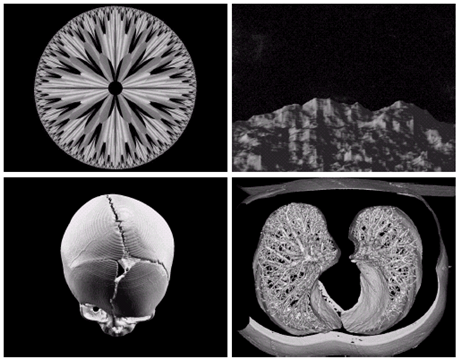

Gamma ray image

- 감마선의 투과성을 이용

- 주요 응용분야: 핵의학, 천문관측

a) 환자에게 감마선을 방사하는 방사선 동위원소를 주사, 감마 검출기로써 영상을 획득 - 병소의 위치 파악에 유용

b) PET(positron emission tomography) image

c) 백조자리 15,000년전의 가스성운의 감마선 영상

d) 핵반응 밸브로부터 나오는 감마선(밝은 부분)

X-ray image

Other imaging modalities

- 지진 모델의 단면영상(화살표는 석유와 가스 트랲을 가리킴)

a)아기1 b)아기2 c)갑상선 d)손상된근육

- 전자현미경: SEM(scanning electron microscope)

- 전자빔을 쏘아 각 위치에서 빔과 샘플과의 상호작용을 기록

텅스텐필라멘트의 250x SEM영상, 손상된 IC의 250x SEM영상